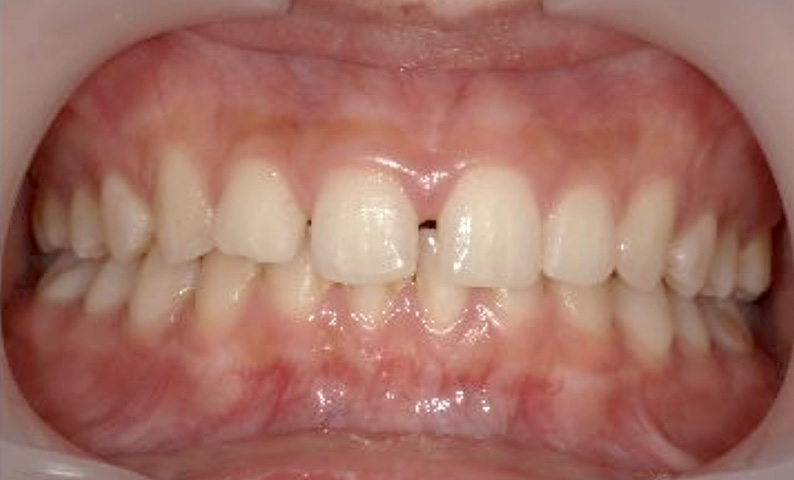

症例_024 上下顎の部分矯正

治療期間:13ヶ月金額:51万円+税女性前歯のガタガタ八重歯